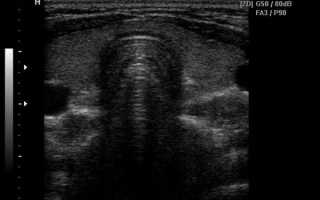

Эхограммы щитовидной железы

На эхограмме щитовидка представлена в виде подковы с вогнутостью, обращенной кзади и состоит из двух долей, разных по размеру. Доли соединены между собой тонким перешейком. Контуры органа четко очерчены в норме, структура железа однородная мелкозернистая нормальной эхогенности. В поперечном сканировании железа до 8 см в норме, переднезадние размеры долей не более 2 см, в перешеек до 7 мм, при этом его размеры не всегда определяются.